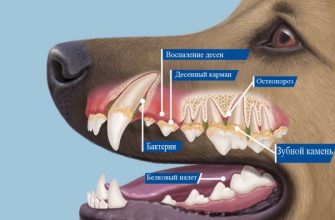

Воспаление ротовой полости, или стоматит, у хаски – это общее название для различных воспалительных процессов, которые могут поражать слизистую оболочку рта. Это может быть гингивит (воспаление десен), пародонтит (воспаление тканей, окружающих зубы), или даже язвы и эрозии на слизистой оболочке щек, языка и неба. Причины воспаления могут быть самыми разными – от плохой гигиены полости рта до серьезных системных заболеваний.

Важно понимать, что хаски, как и любые другие породы собак, подвержены зубному камню и налету, которые являются идеальной средой для размножения бактерий. Эти бактерии выделяют токсины, которые раздражают и воспаляют десны. Если не принимать меры, воспаление может распространиться глубже, поражая костную ткань и приводя к потере зубов.

- Плохая гигиена полости рта: Как мы уже говорили, зубной налет и камень – главные враги здоровых десен. Регулярная чистка зубов, использование специальных лакомств и игрушек помогут предотвратить их образование.

- Неправильное питание: Кормление мягкой пищей может способствовать образованию зубного налета. Сухой корм, наоборот, помогает очищать зубы во время жевания.